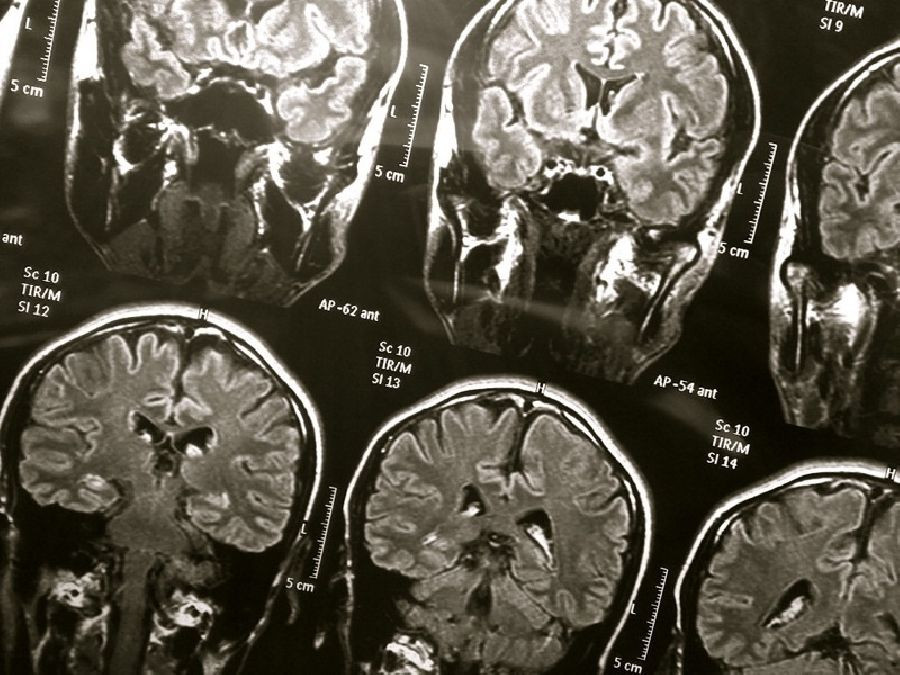

Encuentran una vía para abordar el deterioro de la barrera hematoencefálica en el Alzheimer

Tras desarrollar un modelo de laboratorio de la barrera hematoencefálica humana (BHH), los neurocientíficos del Instituto Picower para el Aprendizaje y la Memoria del Instituto Tecnológico de Massachusetts (MIT) han descubierto cómo el gen de riesgo de enfermedad de Alzheimer más común provoca que las placas de proteína amiloide rompan la vasculatura del cerebro y han demostrado que pueden prevenir el daño con medicamentos ya aprobados para uso humano.

Alrededor del 25 por ciento de las personas tienen la variante APOE4 del gen APOE, lo que los pone en un riesgo sustancialmente mayor de enfermedad de Alzheimer. Casi todas las personas con Alzheimer, e incluso algunas personas mayores sin, sufren de angiopatía amiloide cerebral (AAC), una condición en la cual los depósitos de proteína amiloide en las paredes de los vasos sanguíneos deterioran la capacidad del BHH para transportar adecuadamente los nutrientes, eliminar los desechos y prevenir la invasión. de patógenos y sustancias no deseadas.